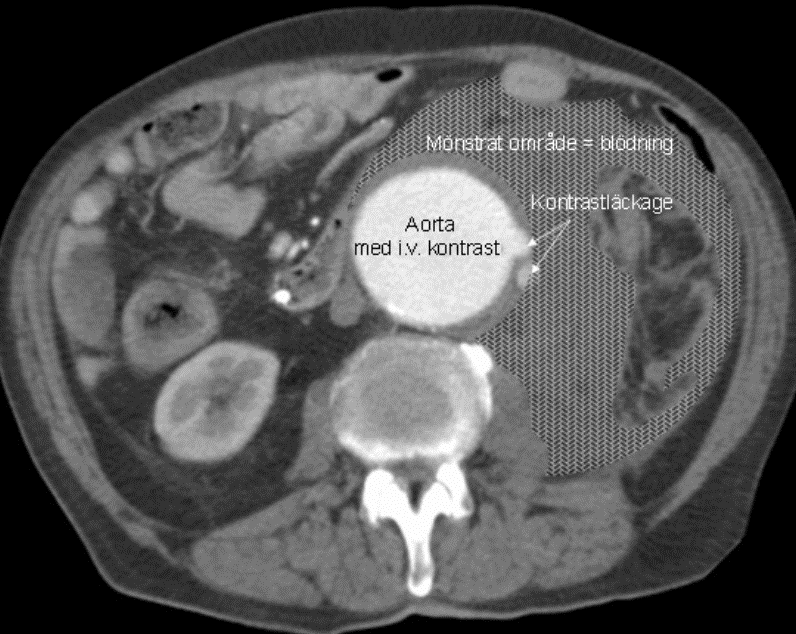

Vad ser du?